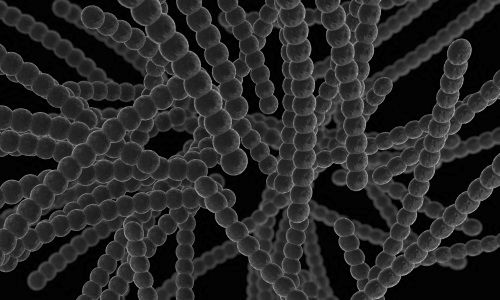

Стрептодермія - це інфекційне захворювання, яке характеризується шкірними проявами і викликається бактеріями класу стрептокок. Стрептодермія у вагітних зустрічається не так часто, цього заразне захворювання більше схильні діти і підлітки до 15 років.

Під час своєї життєдіяльності на шкірі людини стрептококи викликають гнійні, лущаться поразки, найчастіше формою у вигляді кола.

Організм жінки може підхопити будь-яку інфекцію, з якою легко б впорався до вагітності. Збудник стрептодермии - стрептокок - відноситься саме до таких видів інфекції.

Мікрофлора хвороботворних бактерій досить швидко заселяє шкіру жінки, сильно руйнуючи її імунітет. При цьому стрептодермія не спроможна завдати великої шкоди ні матері, ні майбутній дитині і з успіхом лікується.